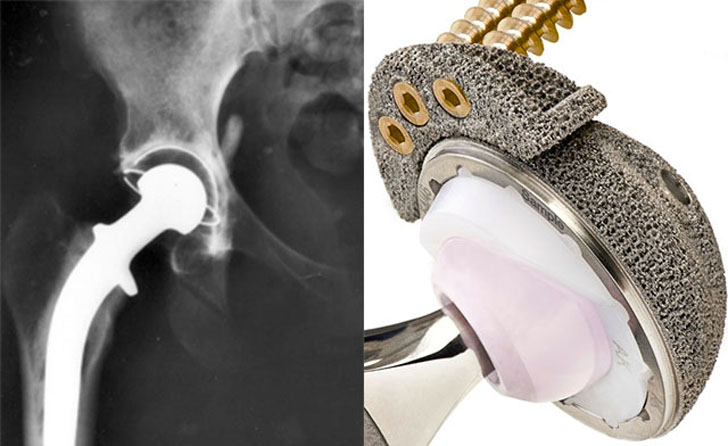

So we know the technology is available. However, applying it for medical use is a little bit more involved. At present, several studies are being conducted to investigate the use of 3d printed titanium implants for hip replacements. Titanium is already used in various prosthesis including hip prosthesis. What 2-d printed prosthesis offers is a cost-effective custom fit that reduces time in surgery as well as recovery. Also because more complex components can be produced easily and efficiently there is an added benefit of creating more biocompatible prosthesis. The rough surface of the image above is by design to encourage regrowth further creating a better fit. These technologies and other on the way make what would have been science fiction a decade ago a reality today.